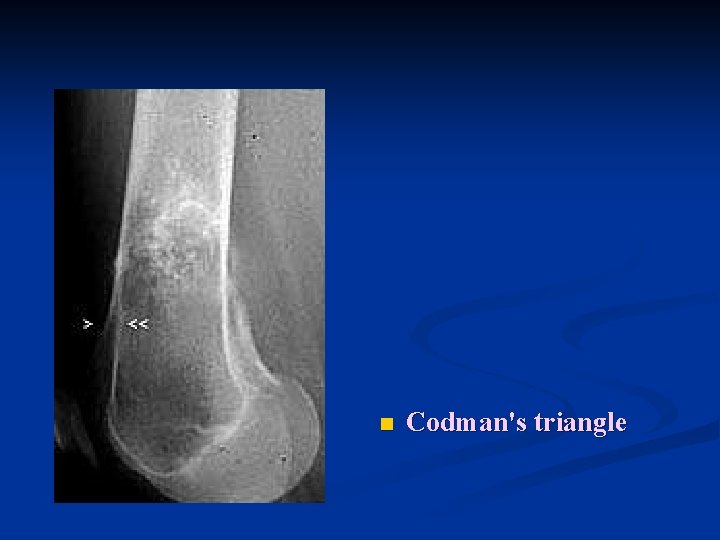

n Codman's triangle

n n n Radiology of a long bone usually show a large, ill-defined tumor. The bone-producing (osteoblastic) lesion is located in the medulla near the metaphysis Lifts up the periosteum (periostal reaction) n n n often producing "Codman's triangle", an angle between the outer cortex and the elevated periosteum, Sun-rays pattern Less common : n destructive (osteolytic) lesions with a "moth eaten" appearance of the cortex.